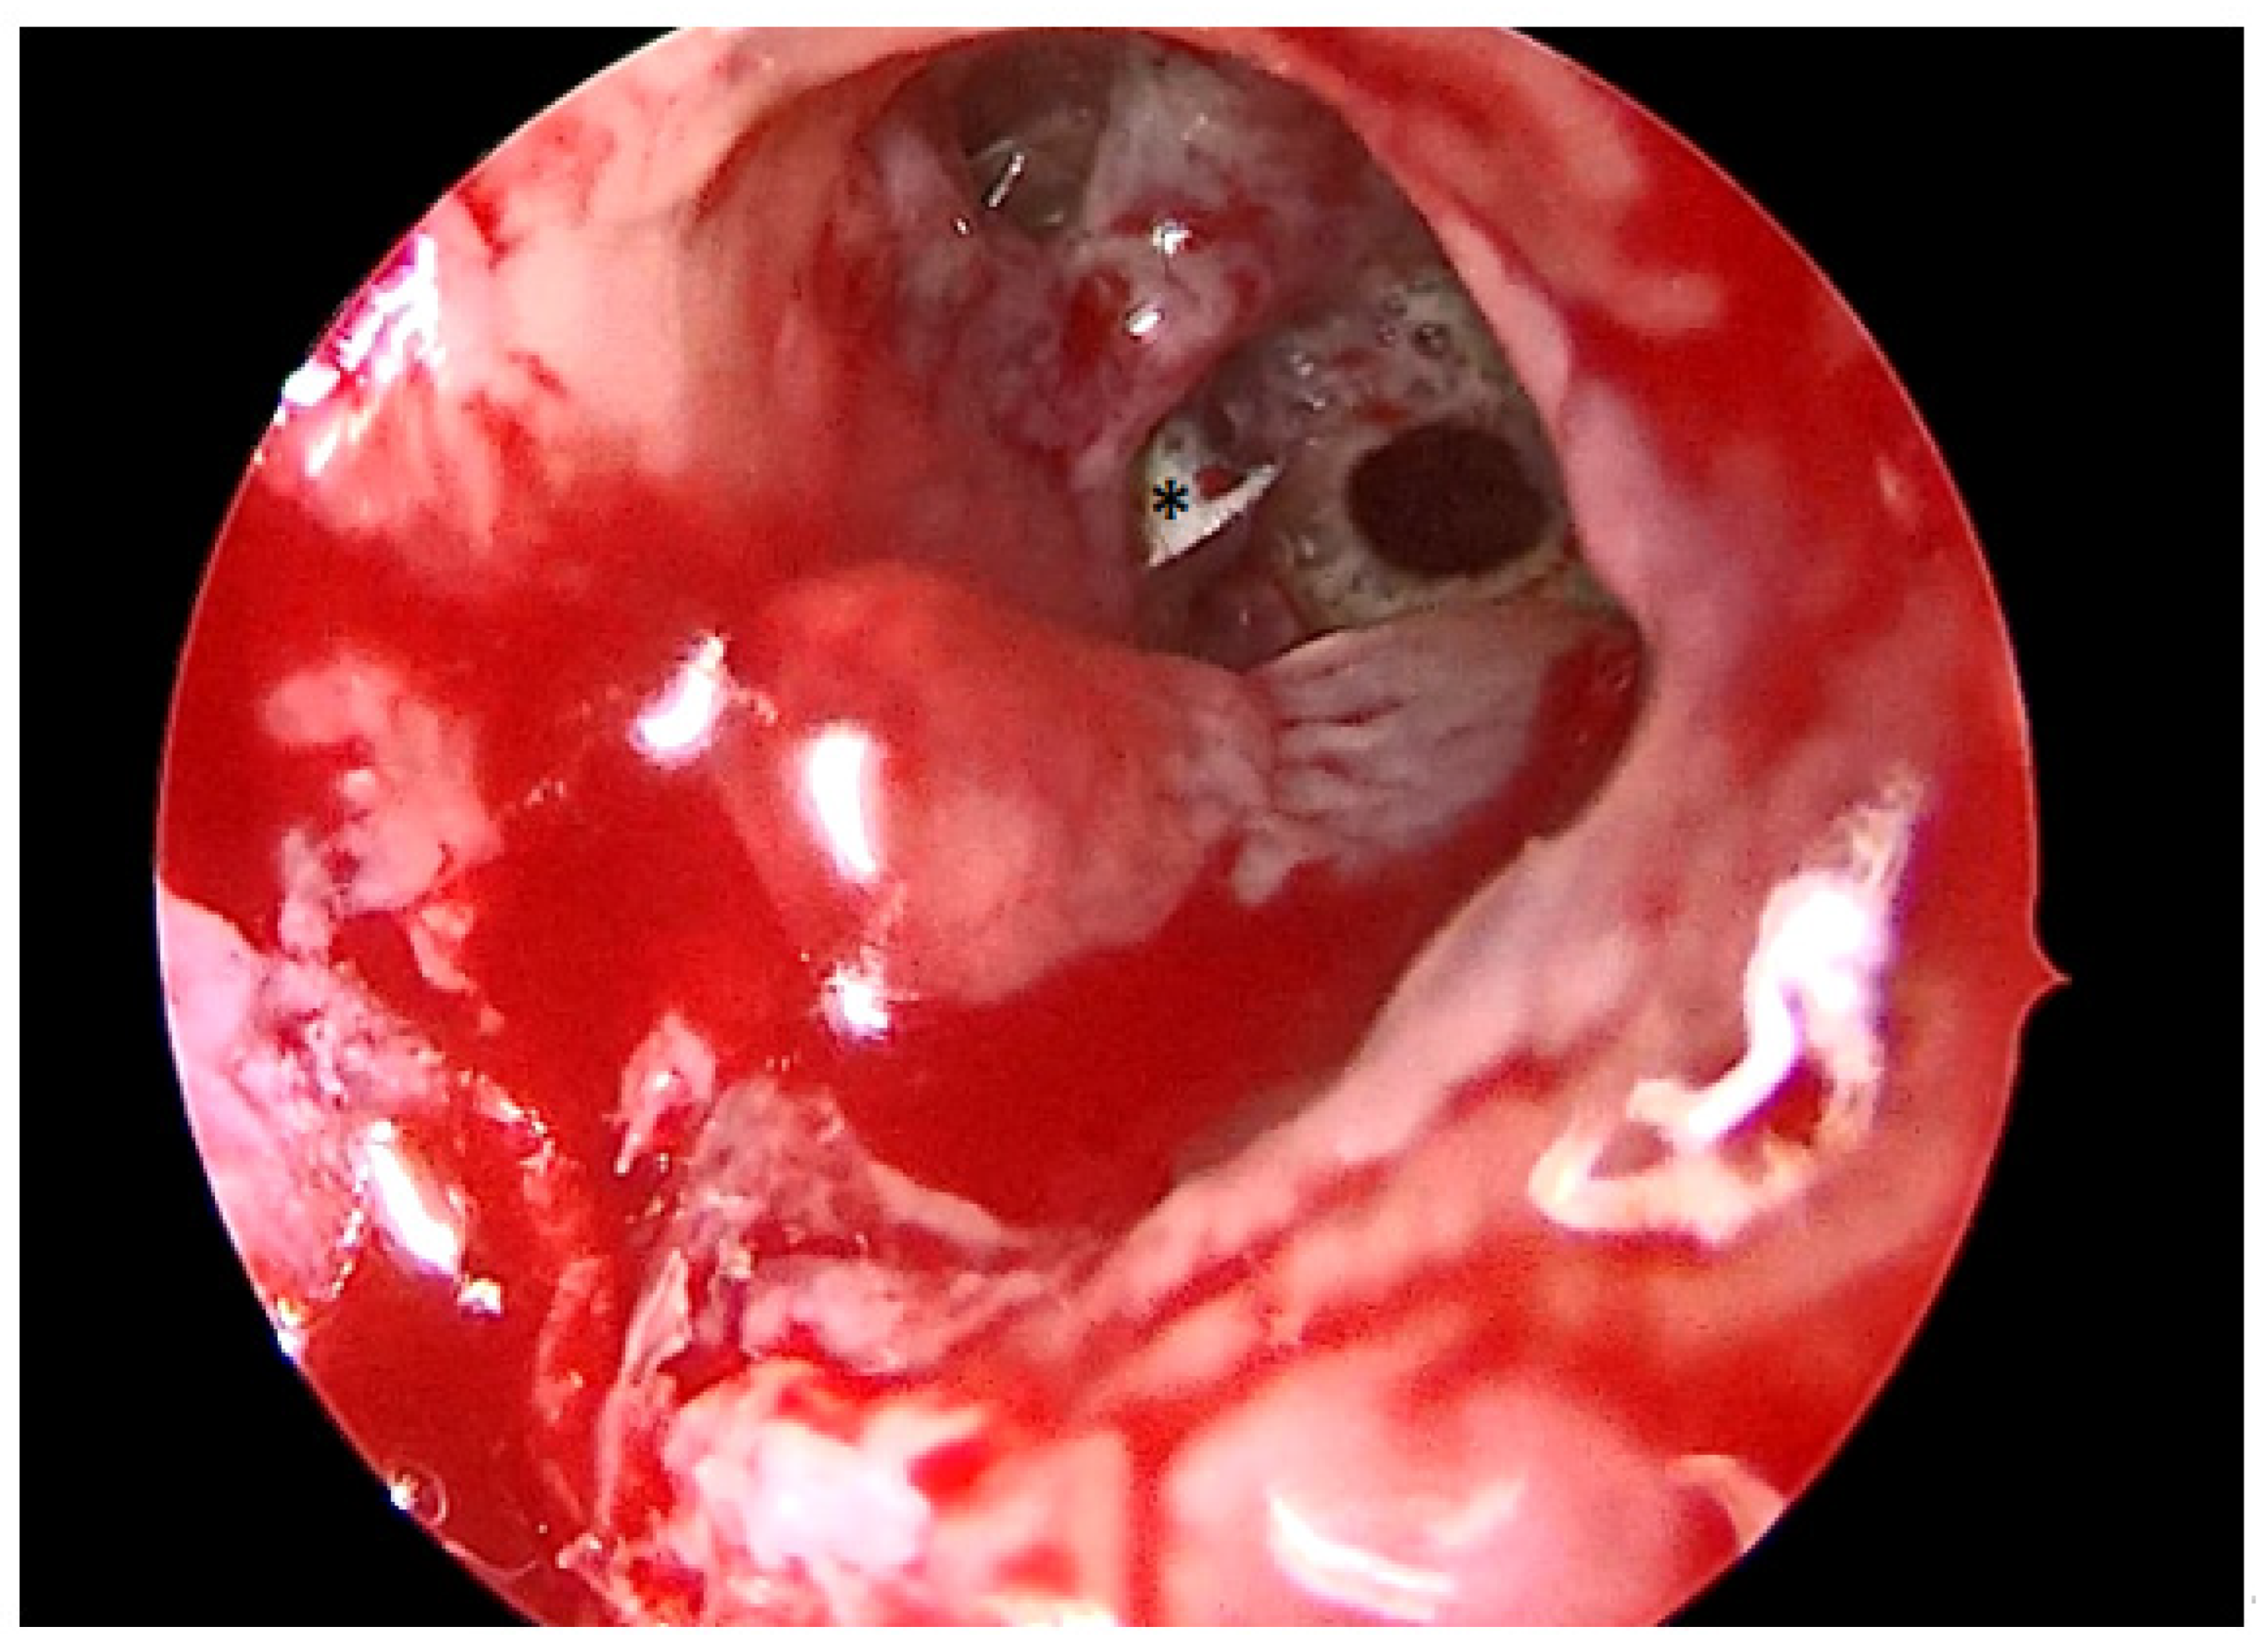

A total of 68 patients responded to the criteria and to the definition as classical odontogenic complications and were included in this retrospective study; of these, 40 were men (59.7%) and 27 were women (40.3%). The mean age was 45.8 years, (the youngest patient was 33 and the oldest 68). All the patients reported a history of previous dental disease or treatment, and the dental origin of the sinusitis was confirmed by anamnestic record, clinical observation, and radiological evidence. Maxillary pain, nasal obstruction, and an anterior or posterior nasal drip were the most referred symptoms. All patients were resistant to medical therapy. All patients underwent a head CT scan before the intervention. All patients had unilateral sinus opacification. A total of 30 patients (42%) reported an obstruction of the osteo-meatal complex (OMC). A foreign body in the maxillary sinus was found in 9 patients (13%) (Figure 1) and an OAC was present in 27 patients (40%) (Figure 2, Figure 3 and Figure 4). The surgical therapy consisted of a combined oral and nasal simultaneous approach for 28 patients (43%), a combined non-simultaneous approach for 4 patients (6%), a nasal only approach for 14 patients (21%), and an oral only approach for 20 patients (30%) (Figure 5).

Figure 2. Intraoperative photo of the maxillary sinus seen from the OAF. * = Maxillary foreign body.